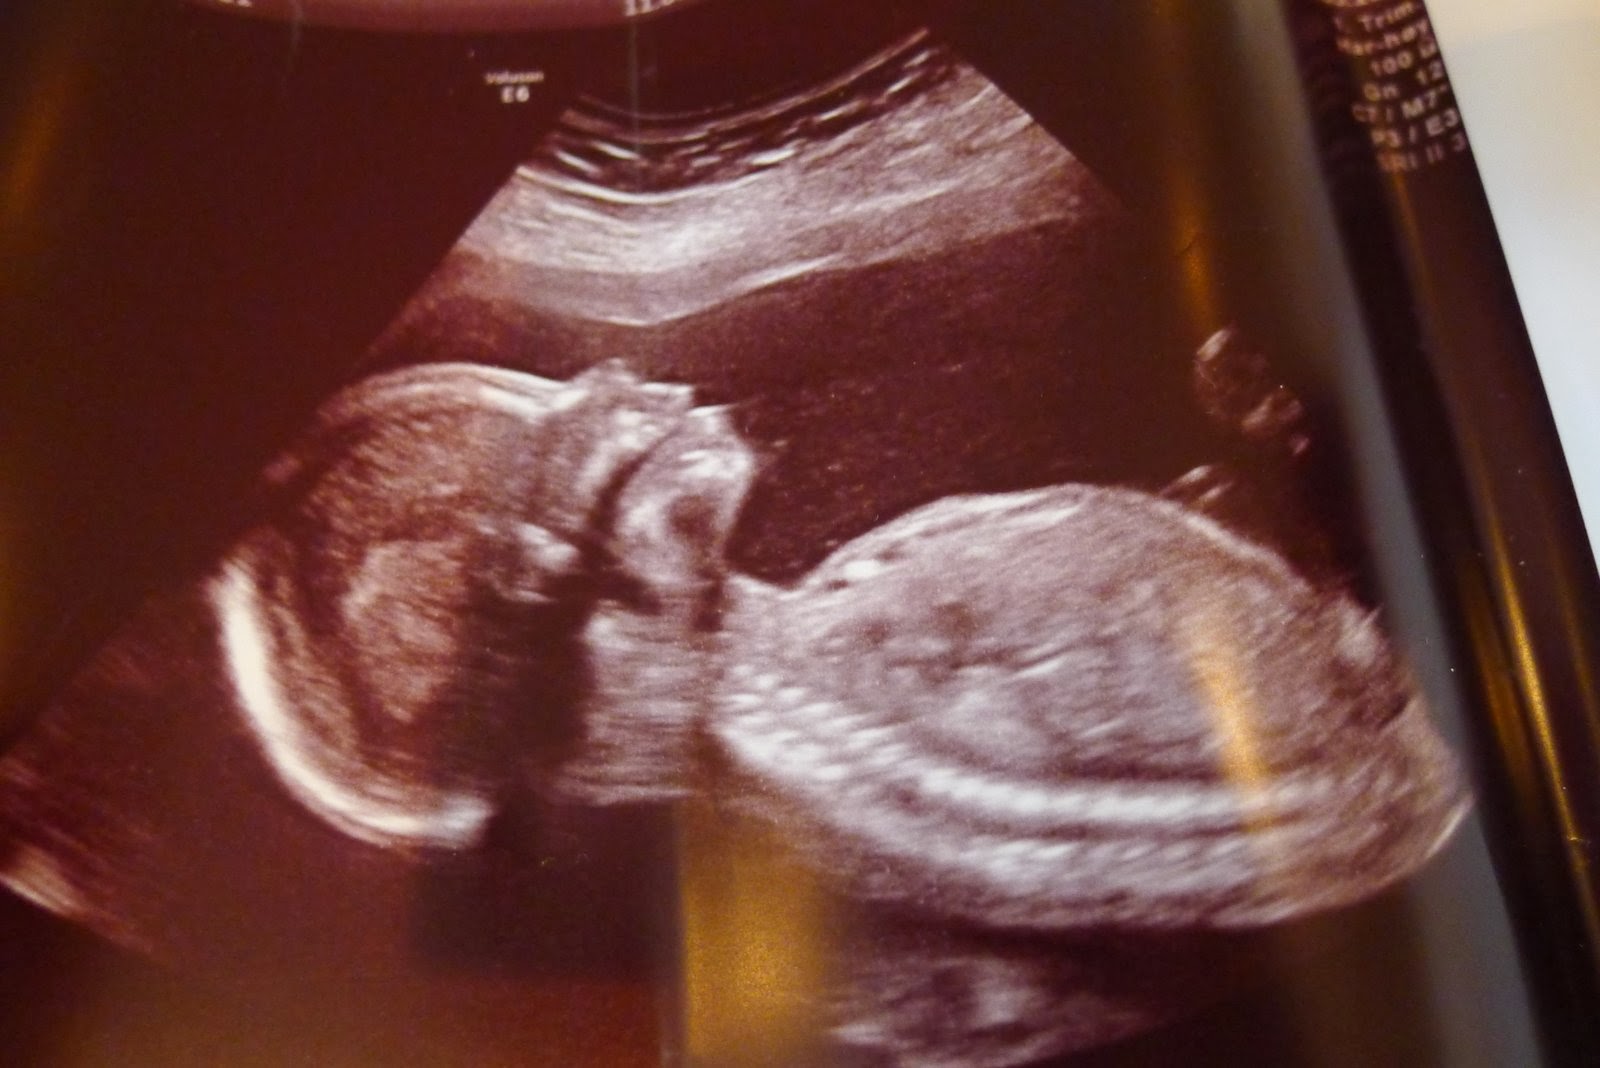

Vi venter en jente!

Idag var vi på ultralyd og jeg er ca 19 uker på vei. Det medisinske så fint ut og jeg har fått ny terminato som er 13 februar:)

Jordmoren var ganske klar- det er en liten tulle som ligger i magen min. Det er også det de andre gynekologene har trodd.

Vi er selvsagt svært glad!